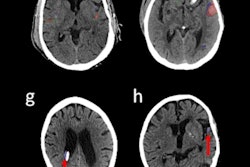

Seyam's group conducted a study that assessed the effect of incorporating into their emergency department workflow a commercially available deep-learning algorithm (Aidoc) to diagnose intracranial hemorrhage on CT. The team then compared the algorithm's diagnostic performance to preimplementation diagnoses of the condition. The study included 4,450 patients who underwent emergency head CT; of those, 3,017 had exams after the AI algorithm had been implemented.

Incidence of intracranial hemorrhage was similar in both groups (pre-AI, 14.4%; post-AI, 14.3%). Regarding the AI-based algorithm's performance for detecting ICH, the team found the following:

The authors noted that the algorithm had high rates of detection for ICH (97.1%) but lower rates for subarachnoid hemorrhage (80%) and subdural hemorrhage (69.2%), indicating that "a false sense of security using AI is a pitfall that must be addressed, particularly for certain subtypes of ICH and in acute care applications," they wrote.